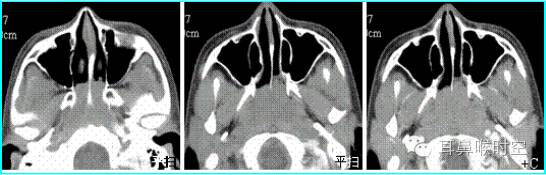

C T— computed tomography

咽部正常CT表现

(1)鼻咽腔层面:

CT检查扫描方法

①鼻咽部轴扫:常规OML (听眦线)

扫描体位:标准仰卧头颅正位

扫描参数:OML基线,层厚3mm/5mm,螺距1.0。

扫描范围:以侧位作为定位线,包括中耳乳突进行螺旋方式扫描

部分进行静脉增强扫描;

CT 观察与测量方法

①标准CT 轴位:主要观察12项结构

鼻咽腔的形态

腺样体大小与形态

咽隐窝

咽鼓管咽口

圆枕

鼻后孔的阻塞情况

翼内外板

翼内外肌

咽旁间隙

邻近骨质有无破坏

鼻旁窦

中耳乳突等。

标准CT 轴位像:

鼻咽气腔形态因层面不同而不同,其中,呈梯形(图3),长方形(图4)。

咽隐窝及咽鼓管咽口清晰或隐约可见,双侧对称,鼻后孔大部分畅通,咽旁间隙清晰,邻近骨质无破坏。

鼻咽气腔形态

梯形 长方形

分型

儿童腺样体肥大依据CT 表现分为3 型:

CT表现:

为鼻咽顶后壁增厚,形成肿块

前缘平直或略凹陷,堵塞后鼻孔

鼻咽腔变形、狭窄,上气道变窄。

鼻咽气腔均不同程度变形变窄(图7,8) , 不规则形,横条形,完全闭塞。

增大的腺样体呈软组织密度,均匀一致,与头长肌相近,呈弥漫性肿块形(图9)、嵌入鼻后孔肿块形(图10)、单侧肿块形(图11)。

静脉增强扫描呈轻-中度强化。